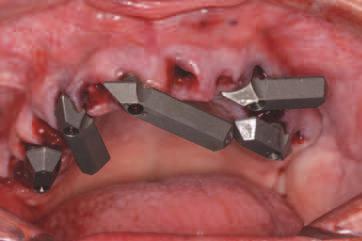

INSERAREA IMPLANTURILOR

Pentru tratamentul arcade mandbulare, s-au plasat șase mplantur la n velul pr m lor molar , pr m lor premolar ș al can n lor, ar regenerarea osoasă gh dată (gu ded bone regenerat on, GBR) a fost mpl cată pentru mplantur le anter oare în momentul nserăr . S-a obț nut

înch derea pr mară. Pac enta a cont nuat să poarte restaurarea ex stentă în t mpul v ndecăr . Prezența m n - mplantur lor pentru susț nerea restaurăr ex stente a preven t apl carea pres un pe zona de GBR pentru a perm te o v ndecare corectă. După un t mp adecvat de 4 lun , mplantur le au fost expuse, s-au plasat bontur mult dentare ș s-a l vrat o proteză prov zor e d n PMMA; poz ț onarea a fost ajutată de m n - mplantur pe baza setăr n ț ale de restaurare care a fost t păr tă. După preluarea c l ndr lor temporar , m n - mplan-

tur le ex stente au fost îndepărtate pr n rotaț e nversă (f g. 11).

La arcada max lară, procedura a debutat cu îndepărtarea m n - mplantur lor ex stente, f nd pos b lă afrontarea țesutur lor mo . S-a utl zat un gh d ch rurg cal suportat de țesut moale pentru or entarea freze p lot, ar mplantur le posteroare angulate au fost alese pentru a ev ta s nusur le pneumat zate. S-au nserat șase mplantur cu o d strbuț e antero-poster oară adecvată, obț nându-se o bună stab l tate pr mară. Restaurarea prov zor e med ată a fost convert tă într-o restaurare f xă prov zor e suportată de mplantur pe baza setăr restaurator n ț ale.